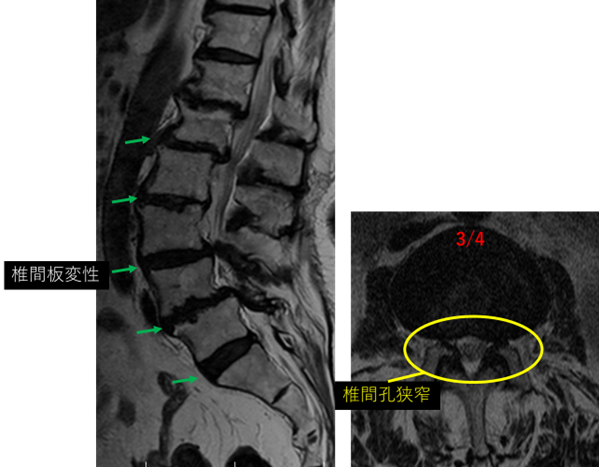

L1/2: 変性、膨隆、左椎間孔狭窄

L2/3: 変性、膨隆、右椎間孔狭窄

L3/4: 変性、膨隆、左椎間孔狭窄

L4/5: 変性、膨隆、両側椎間孔狭窄

L5/S: 変性、膨隆

以上の事が画像上認められます。

L1/2、2/3、3/4、4/5 に

椎間板変性、椎間孔狭窄 を認め、主症状の原因の可能性が高い。